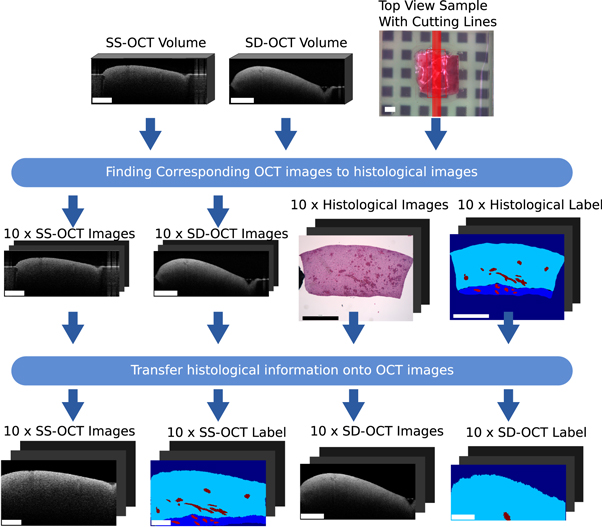

2.3. Work-flow and registration pipeline

This section covers the work-flow which transferred the histological information onto corresponding OCT images of the two OCT systems. The general registration pipeline is displayed in figure 3. The acquired data per sample consists of two OCT volumes (one per system), a white light image, which shows the top view of the sample, and ten labelled histological cuts. The position of the histological cuts are marked on the white light image. The first step of the process is to identify OCT images corresponding to the histological cuts. For this identification, the basic idea is to transfer the cutting lines, which represented the position of the histological images, onto the OCT volumes. The corresponding OCT images were then extracted along the transferred cutting lines. The second step is the transfer of the histological information onto the OCT images. This step consists of a non-rigid registration between the histological image and the OCT images based on the outer shape information of the sample, because inner structural features are usually not present. Finishing this work-flow results in a labelled dataset of OCT brain images acquired by two different OCT systems.

Figure 3. Overview of the work-flow of the transfer of histological label onto corresponding OCT images. The rectangle in the bottom left of each image has the length of 1 mm.

Download figure:

Standard image High-resolution image2.3.1. Finding OCT images corresponding to the histological cuts